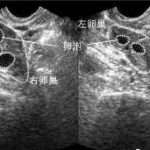

三代试管又称为PGD/PGS,是指在体外受精过程中,通过对卵子或胚胎进行基因诊断和筛查,选择优质的胚胎进行移植,从而提高妊娠率和降低遗传疾病的发生率。目前,运城地区已经具备了开展三代试管技术的条件和能力。

三代试管技术主要包括两个部分:第一部分是基因前期诊断,即在受精前通过取样检测胚胎携带的遗传病变;第二部分是基因筛查,即在受精后通过取样检测胚胎染色体异常情况,以避免常染色体异常等问题。整个过程需要借助多种先进设备和技术手段。

在三代试管技术中,通常会选择最优质的一个胚胎进行移植,以避免多胎妊娠等风险。但有研究表明,在某些情况下,将两个优质胚胎同时移植可以提高妊娠率和活产率。具体是否采用这种策略需要根据具体情况进行判断和决定。